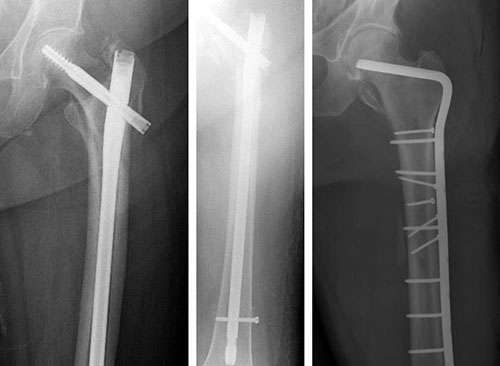

Femur, Shaft - Fracture 32B2 - Intramedullary Nailing With the Expert Lateral Femoral Nail (LFN). Intramedullary Nail For Intertrochanteric Hip Fracture are a theme that is being searched for and appreciated by netizens nowadays. You can Save the Intramedullary Nail For Intertrochanteric Hip Fracture here. Save all royalty-free pics. INTRAMEDULLARY NAIL FOR INTERTROCHANTERIC HIP FRACTURE, TECHNIQUE AND SOUND UNSTABLE TROCHANTERIC HIP FRACTURE TREATED WITH MINIMALLY INVASIVE TECHNIQUE: .

Femoral Shaft Fracture Intramedullary Nailing (Femur Fracture Surgery) - Intramedullary Nail For Intertrochanteric Hip Fracture

This is an example of a surgery to fix a femur (thigh bone) fracture utilizing an intramedullary nail. This is a minimally invasive way of fixing this surgical problem and allows for immediate range of motion and full weight-bearing.